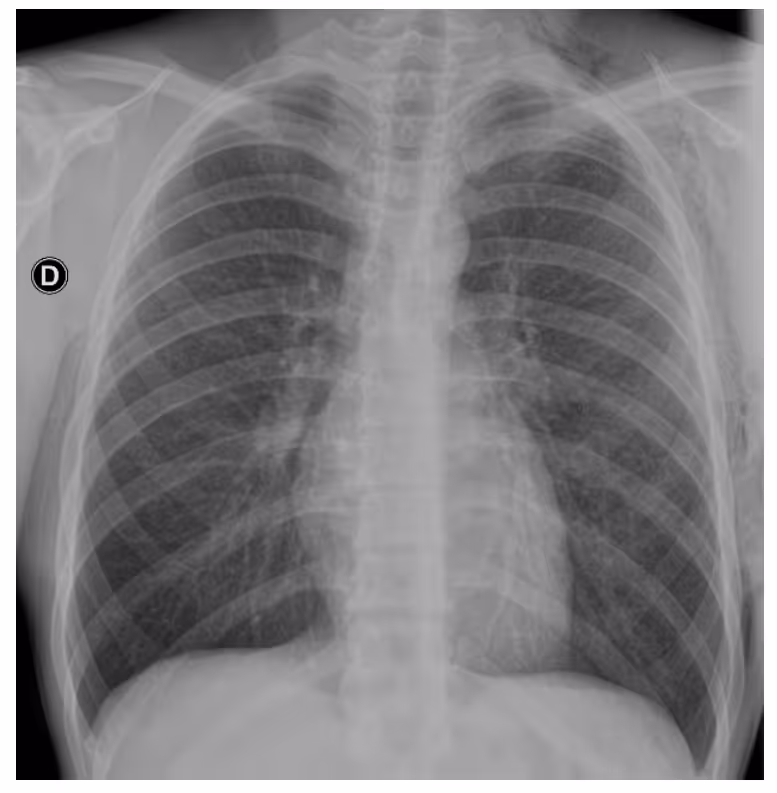

- Image findings:

- Chest radiograph revealed a left pneumothorax, marked by the visible left pleural edge

- No shift of the mediastinum

- Extensive subcutaneous emphysema over the left chest wall